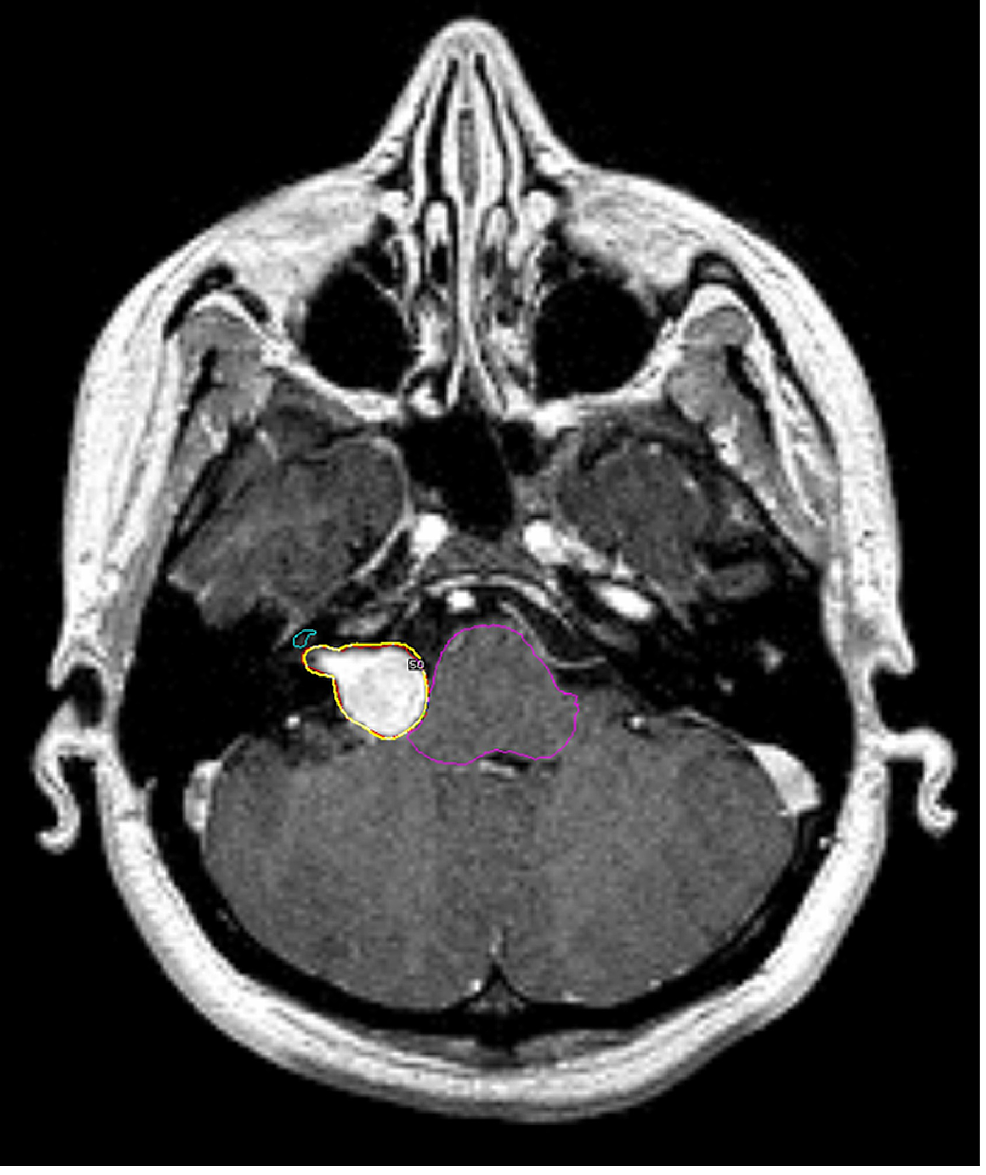

From wiki.cancerimagingarchive.net

Segmentation of Vestibular Schwannoma from Resonance Imaging Radiology Vestibular Running through this bony canal is a tube called. 1 vss may remain within the internal auditory canal (iac) or extend into the cpa. From these special sensory organs of the inner ear, the vestibulocochlear nerve transmits afferent impulses to the central nervous system encoding auditory stimuli,. Vertigo is caused by a disturbed vestibular system and is subdivided into peripheral. Radiology Vestibular.

From radiopaedia.org

Vestibular schwannoma Image Radiology Vestibular 1 vss may remain within the internal auditory canal (iac) or extend into the cpa. Running through this bony canal is a tube called. The vestibular aqueduct is a narrow bony canal (aqueduct) that connects the endolymphatic sac with the inner ear (vestibule). Vestibular schwannomas (vss) are the most common intracranial nerve sheath tumor, arising from the vestibular division of. Radiology Vestibular.